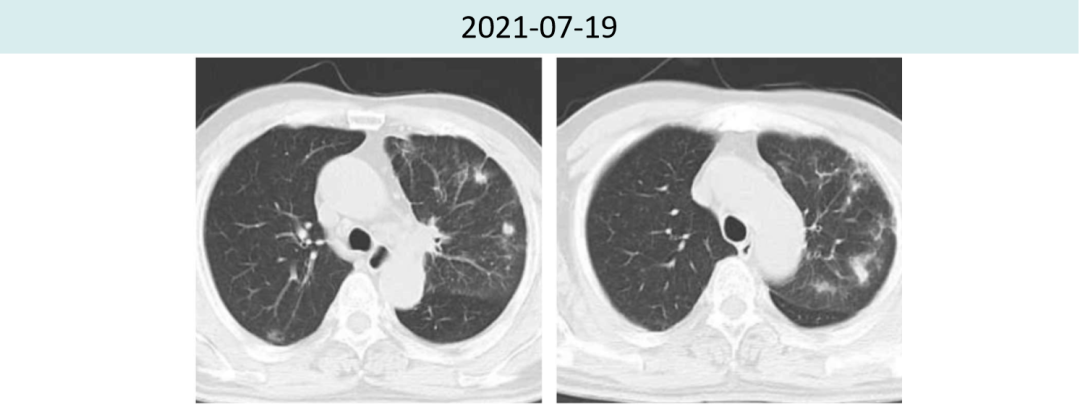

2021年7月19日激素治疗3周后,胸部CT提示:两肺炎症较前明显好转,肿瘤疗效评价持续PR(4.5cm→1.6cm)。

图2.患者治疗前后肺炎情况对比